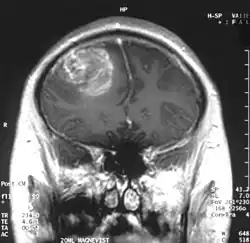

MRI scan showing a glioblastoma with contrast enhancement

Magnetic resonance imaging (MRI) with contrast is the primary imaging modality for diagnosing brain and spinal cord tumors due to its high-resolution visualization of soft tissues. MRI helps identify the tumor's location, size, and potential impact on surrounding structures. In emergency situations or when MRI is contraindicated, a CT scan can be used as an alternative.[12]